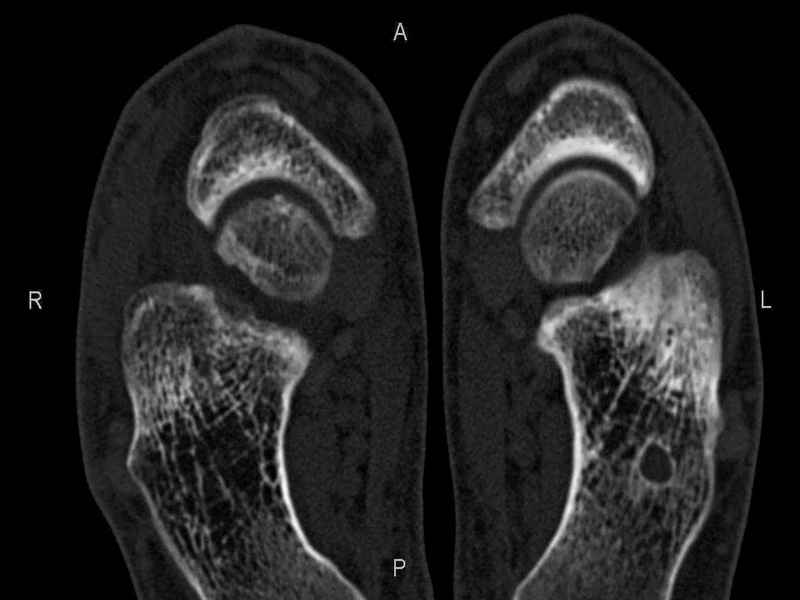

Уважаемые коллеги, обратился за помощью пациент, мужчина, 25 лет. С жалобами на болевой синдром в области голеностопного сустава и среднем отделе стопы. Травму отрицает. Со слов, болевой синдром в течении 1 года. Последние 1-1.5 мес периодически вынужден пользоваться костылями. После ограничения нагрузки боли уменьшаются.Соматически здоров. До появления болей активно занимался рукопашным боем. На СКТ картина рассекающего остеохондрита блока таранной кости, киста шейки таранной кости с признаками импрессии суставной поверхности. А также - разрастания переднего края б\берцовой кости сопровождающиеся клиникой импиджмент синдрома. Предполагаемый план лечения- удаление свободного фрагмента суставного хряща из трансмаллеолярного доступа с рассверливанием поверхности дефекта, кюретаж кисты шейки с заполнением полости биокомпозитом + дебридмент переднего отдела голеностопного сустава. Прошу высказать своё мнение, за и против, предполагаемого плана лечения. А также по возможности ответить на вопросы: 1. Есть ли необходимость в улучшении васкуляризации таранной кости (например подтаранный артродез). 2. Учитывая планируемое применение биокомпозитного цемента целесообразно ли заполнение им дефекта блока таранной кости с моделированием края суставной поверхности.